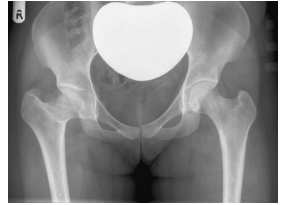

A proteção gonadal em radiografias de quadril e fêmur é um item muito importante da proteção radiológica.

Baseado na imagem abaixo, assinale a afirmativa correta.